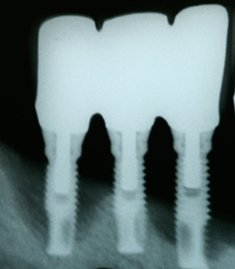

When replacing a missing tooth, bone loss within the socket can compromise esthetic and functional outcomes. For example, if you are considering implants, the compromised bone may not be strong enough to hold the implant, leading to metal exposure, food traps and ultimately loss of the implant.

Adding bone to the extraction socket helps to preserve the thickness, volume and density of the bone, allowing for more predictable implant placement and restoration.